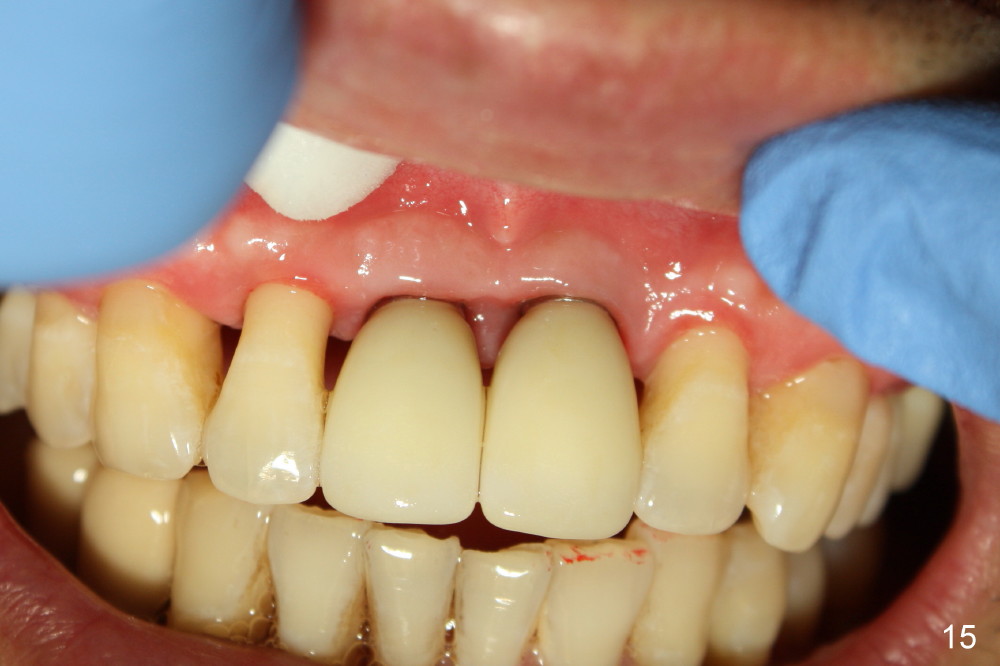

Definitive restoratons (Zirconium crowns) are seated (Fig.15,16). There is no sign of infection. The patient is pleased. In fact the nasal floor does not seem to have been lifted by the implants, as revealed by CT taken 5 years post cementation (Fig.17,18).